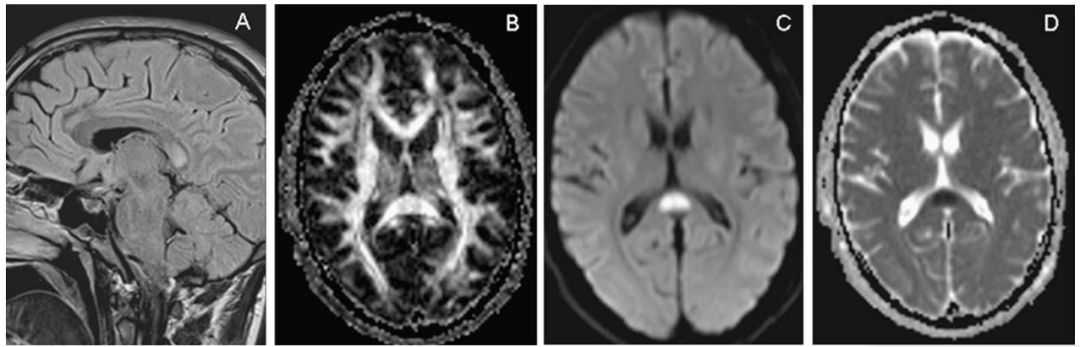

桥脑中央髓鞘溶解

这是渗透性脱髓鞘综合征中的一种类型,属于脑桥基底部的急性髓鞘溶解性病变,多见于快速纠正低钠血症和酒精中毒。组织病理学上是一种非炎症性脱髓鞘,而神经元和相关轴突相对保留,伴少突胶质细胞数量减少和巨噬细胞浸润。病灶呈现“蝙蝠翅”征、“三叉戟”征或“猪鼻”征。

颅脑MRI示:脑桥基底部T1WI低信号

T2WI和FLAIR高信号

病灶呈对称分布

“蝙蝠翅”征 “三叉戟”征 “猪鼻”征